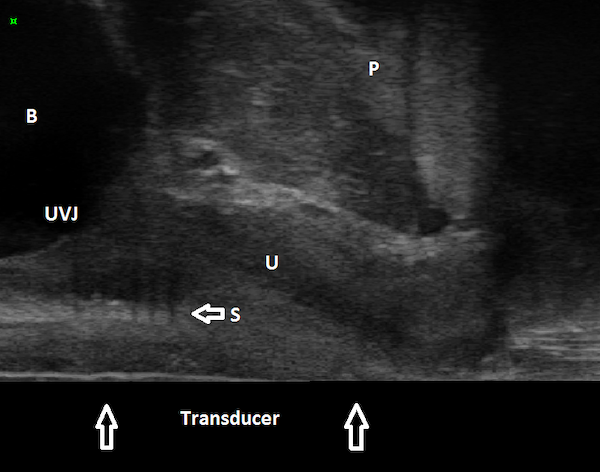

Figures 1, 2, and 3 are mid sagittal plane cut sections of 3D cubes obtained of the anterior pelvic compartment using an endovaginal transducer (BK Profocus Ultraview, Peabody, MA).

Figure 2

Endovaginal 180 degrees anterior compartment image in the midsagittal plane (transducer in the vagina scanning anteriorly): transobturator sling is seen to lie beneath proximal urethra B: Bladder; U: Urethra; S: Sling; UVJ: Urethrovesical junction; P: Symphysis pubis

The sling can be seen located mid-urethrally in Figure 1, underneath proximal urethra in Figure 2, and proximal to the urethrovesical junction in Figure 3, a year after surgery. Whether sling location impacts surgical outcome is a matter of controversy. Dietz et al (2004) concluded that variations in sling placement have little effect on symptom resolution and patient satisfaction in a study of 142 women whose outcomes were evaluated 5 weeks to 2.1 years following TVT sling surgery. Using transperineal ultrasound, the tape position in their study was found to vary from 30 mm above to 12.7 mm below the symphysis pubis at rest and between 15 mm above to 18.7 mm below the symphysis pubis on Valsalva. However, in an unmatched case-control study of 100 patients who underwent Monarc transobturator sling surgery, our group found that the sling location was significantly more proximal in those who had failed sling surgery when compared with those who had succeeded. In 90% of the patients in whom the sling had favorable outcomes, the sling was found to be located either beneath the āhigh pressure zoneā of mid-urethra or at the junction of the proximal and mid urethra (Hegde et al 2013).